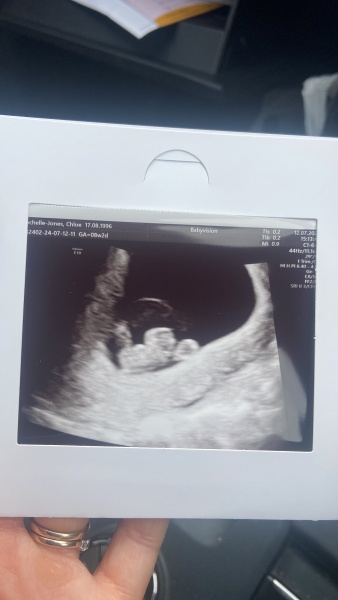

Baby was ok, dating just right. It’s not helped massively but for now it’s nice to know that baby is still growing. I’ve never had a scan where the baby looks like a little baby and it’s nice to have that keep sake as it’s all I’ve ever wanted is an actual baby to look at. I just pray this is the one now 4 years of hell feels too long x

@Rockyslife That’s the best news, I’m so pleased for you šŸ’™ beautiful scan picture too!

Oh @Rockyslife I am so happy for you! Hang on to this news and feeling for as long as you can. You have a healthy 8 week old baby in there, and chances of a successful pregnancy are really increased now too. So so pleased for you and what a cute little bean šŸ’œ

@Rockyslife ah that's a lovely scan. Hope it gives a bit of calmness until next week. For now, everything is ok and there is no reason to think otherwise šŸ’š